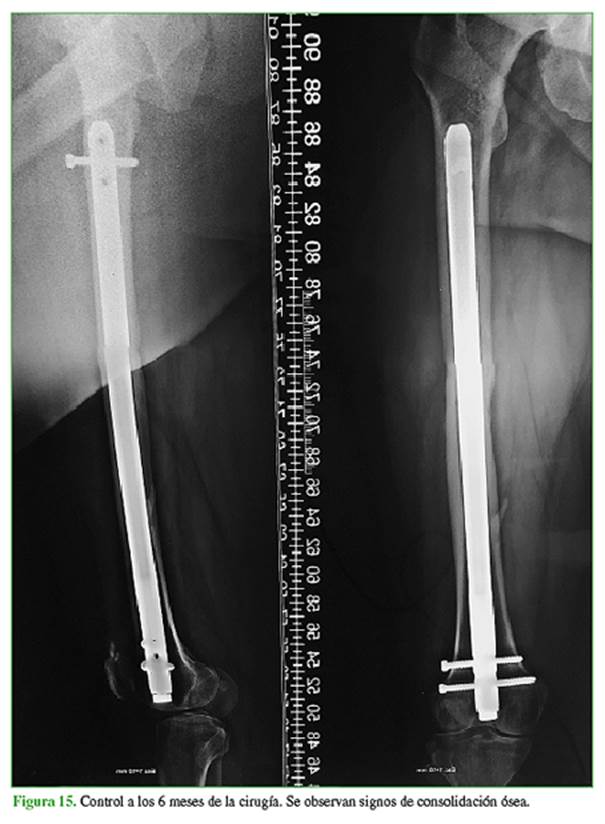

La paciente evolucionó favorablemente y se constató la consolidación a los seis meses en las radiografías de control (Figura 15).